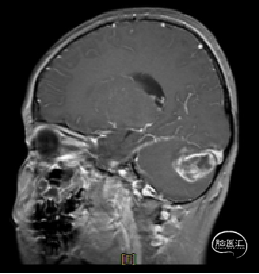

现病史:患者18个月前无明显诱因出现间断头痛,休息后可缓解,开始未予重视,未行特殊治疗。1周前患者无明显诱因出现恶心、呕吐,就诊于当地医院,行颅脑MRI提示:小脑囊实性占位性病变,首先考虑毛细胞星型细胞瘤。现患者为求进一步治疗就诊于我院,门诊以“脑肿瘤”收入院。患者自发病以来神志清,精神可,饮食睡眠正常,二便如常,体重未见明显下降。

术前MRI